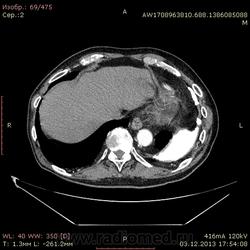

Доброго времени суток уважаемые форумчани! :)Провели исследование КТ грудной клетки с контрастированием, для выявления аневризмы грудного отдела аорты. В результате увидели это:

Для справки: холестериновые камни имеют плотность менее 100 ед.Н. Имеющаяся хренотень в левом гемитораксе имеет плотность больше костной, до 1500 ед.Н. Вопрос: какая химико-физико-биологическая реакция может способствовать превращению мягинькаво холестерина в термоядерную плевральную лепёшку?)

Михаилу Анатольевичу тема для размышлений: а у пациента еще такая же "известь" в содержимом желудка)). У Вас найдётся материал по гастро-эзофаго-плевральным фистулам с соответствующими плотностями?)))